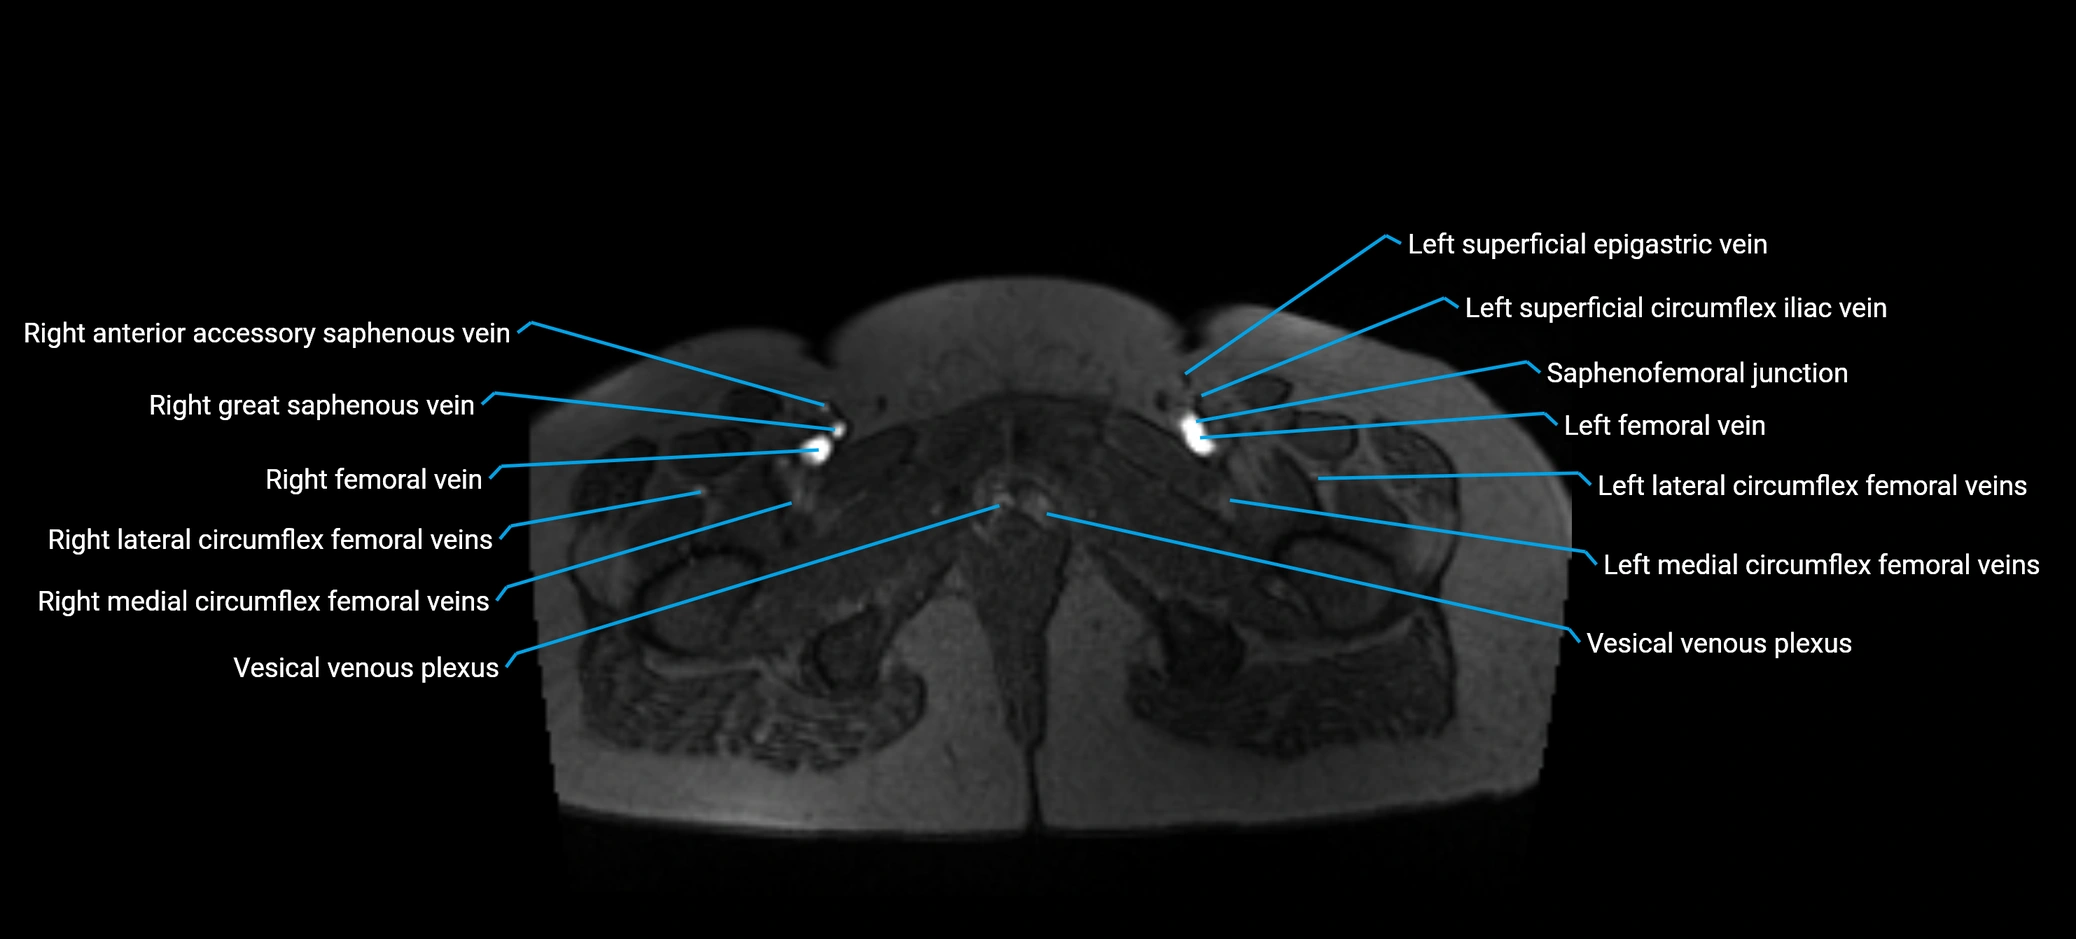

MRV TOF (Time-of-Flight MR Venography):

• Appears as a bright, high-signal vascular channel representing flowing blood

• Clearly shows branching pattern of right portal vein into anterior and posterior branches

• Best in coronal or axial reconstructions for segmental mapping

• No need for contrast, relies on flow-related enhancement

MRI image

image